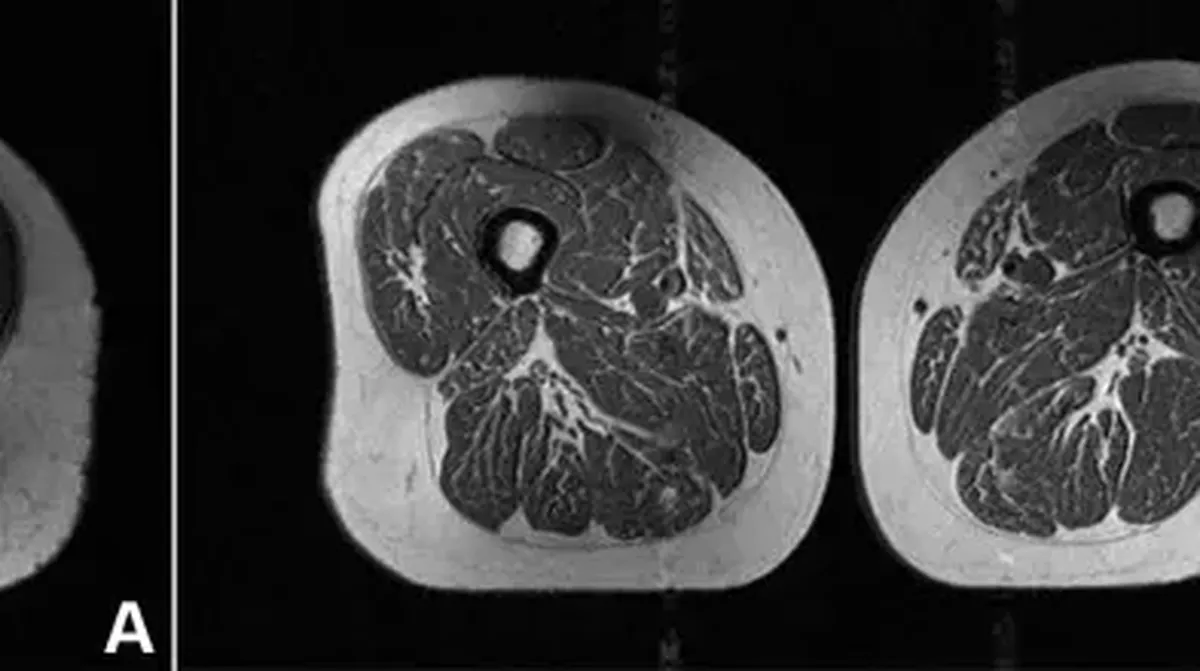

Gambar tersebut sekilas terlihat seperti potongan daging Bersama marbling tinggi, menyerupai steak mahal Bersama garis-garis lemak halus yang melimpah. Akan Tetapi itu bukan Makanan. Itu adalah hasil MRI paha seorang perempuan berusia 62 tahun yang Merasakan 87 persen asupan kalorinya Di ultraprocessed food (UPF).

Di studi tersebut, seorang perempuan berusia 61 tahun juga Memiliki lemak Ke otot pahanya, tetapi tidak separah Perkara Hukum Hukum pertama. Ia mengonsumsi Di 29 persen Makanan ultra-proses Di setahun.

“Ini sangat mengkhawatirkan Lantaran individu-individu ini, yang Di menjalani CT Scan belum Menunjukkan tanda osteoarthritis lutut, sudah Merasakan penurunan Mutu otot,” kata Akkaya.